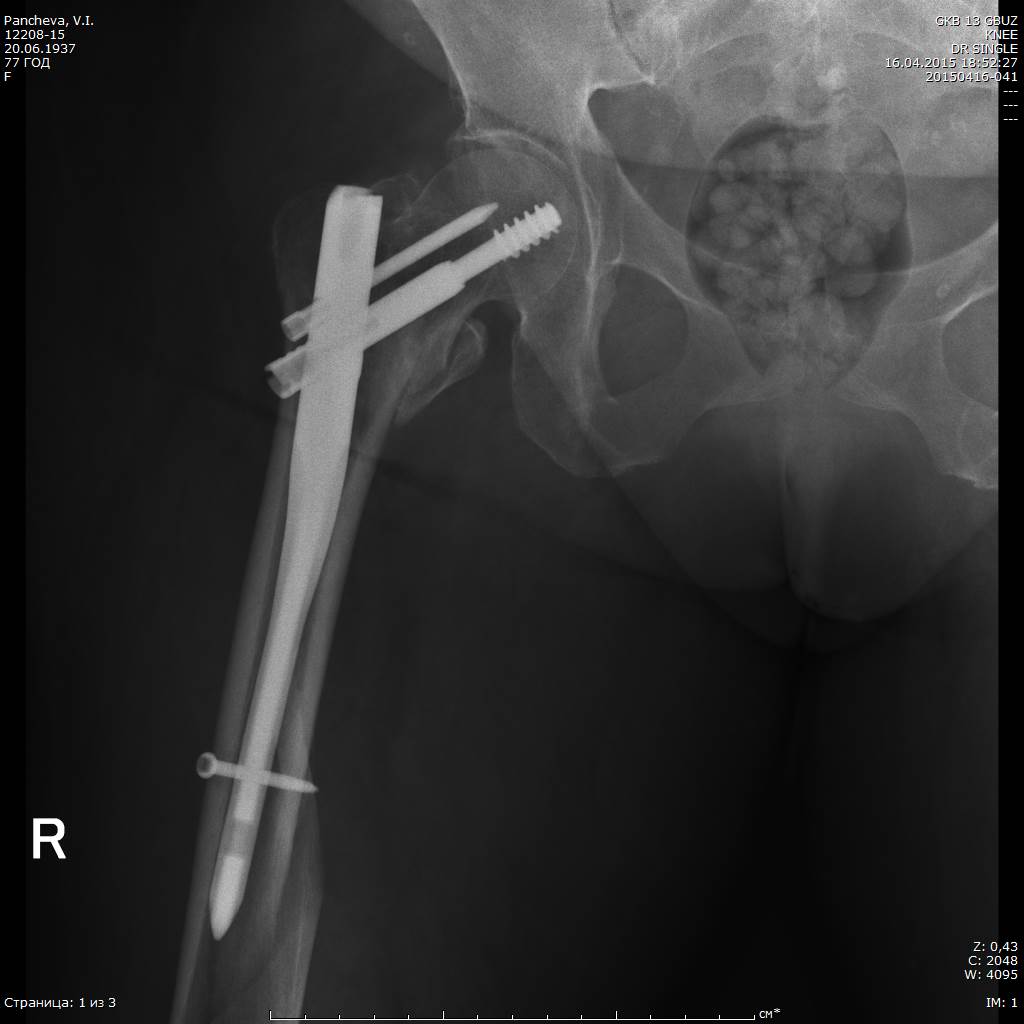

При планировании операции мы с коллегами исходили из следующих посылов:

1. Операция, по возможности, должна быть минимально травматичной и занять наименьшее количество операционного времени. Кровопотеря крайне нежелательна, даже небольшая

2. Операция, по возможности, должна дать пациентке шанс ходить с минимальным использованием дополнительной опоры. Костыли по её кондициям невозможны.

Именно исходя из пункта два был выбран вариант интрамедуллярного ревизионного остеосинтеза.

Вопросы вызывала только необходимость удаления аугментированного клинка, так как такого опыта у нас (в стране?) пока ещё не было. Конечно, в зарубежных статьях я видел, что это возможно, но тем не менее...

А тем не менее клинок, очевидно, благодаря режущим кромкам каждого из отверстий, через которые цемент и попадает в головку и шейку бедра, удалился безо всякого напряжения.

Цемент реально был "срезан" и остался в головке/шейке.

Ну, а установить новый длинный гвоздь такого же диаметра - не проблема, естественно

Новый клинок так же пришлось аугментировать 3 мл специального цемента.

На момент - пациентка достаточно активна, сидит в кровати подолгу, ходит по палате с методистом.